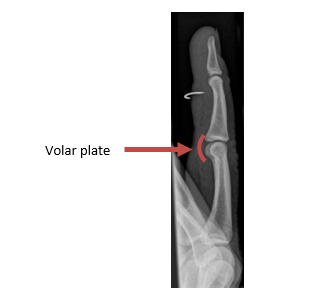

What is a Volar plate?

The volar plate is a strong ligament, not visible on x-ray, at the palm side of the middle joint of your finger. This structure supports the middle joint and prevents it being overstretched backwards or dislocated. The volar plate can be partially or fully torn and may sometimes pull off a small piece of bone (avulsion) when it is damaged.